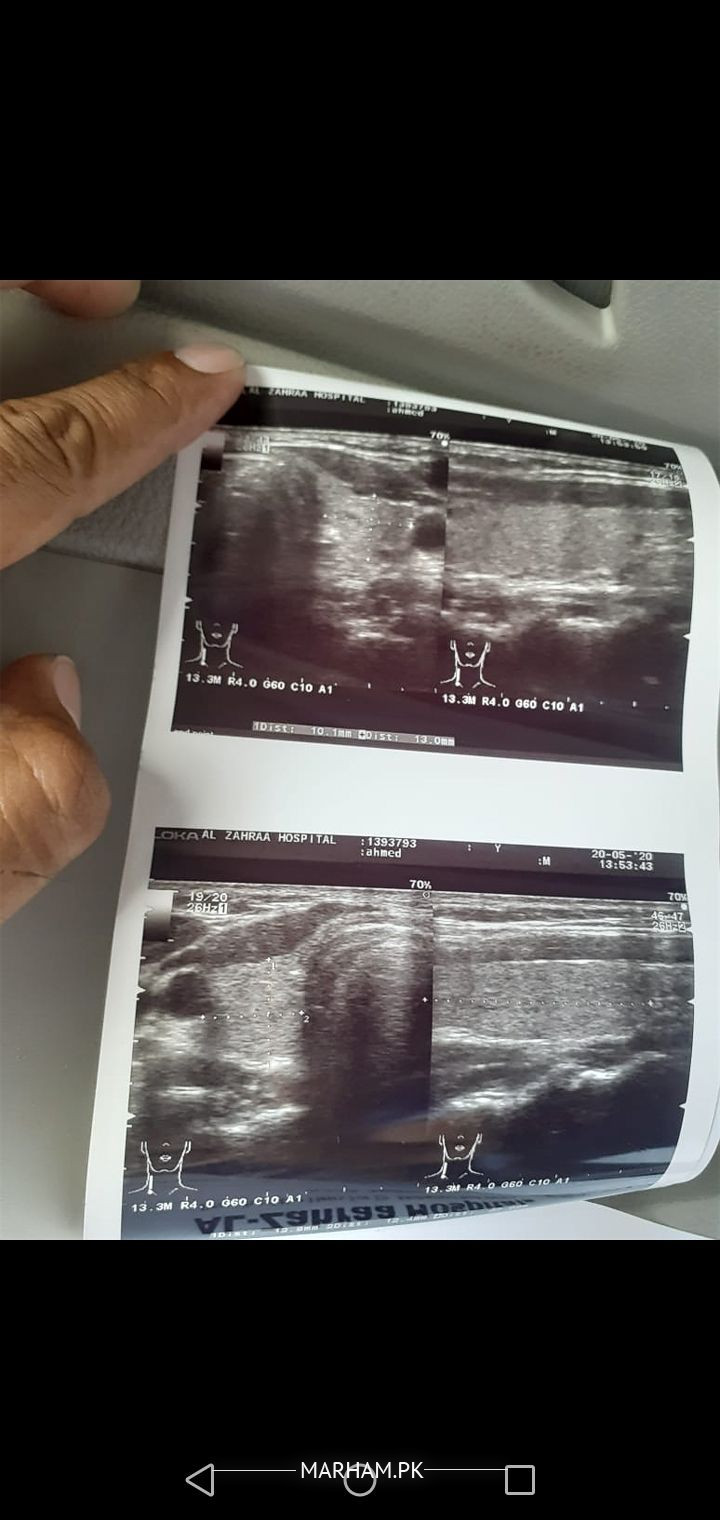

Salam alikum. Mere husband ko 6 months se gally m left side pr jallan or dard hai, 4 months se antibiotics madicine bhi kha rahe hein but abhi tak dard or jallan m koi frk nahi aya infect or ziada bhrti ja rahi hai or left bazu or chest m bhi drd wgra feel horaha hai. Ultrasound m 18 mm ka lymph node show huwa neck m... Ab aagy hme kiya krma chahiye plz koi bataye. Please help

Yeh test likh diya hai doctor n kiya yeh theek hai?